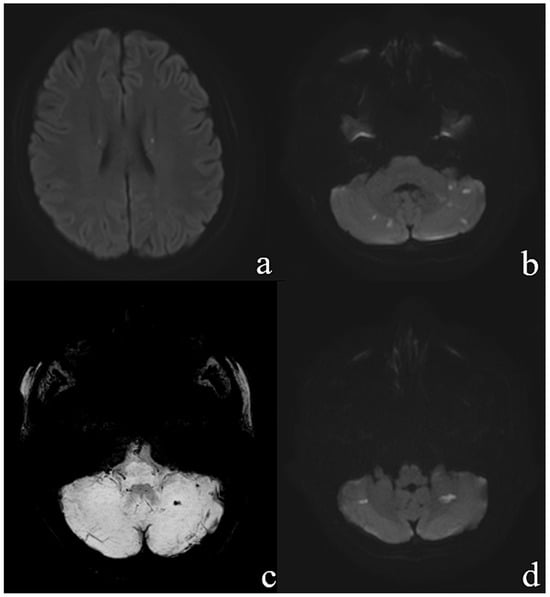

The blood cultures showed a growth of Staphylococcus aureus. Subsequent magnetic resonance imaging of the brain and spinal cord showed multiple diffuse supra- and infratentorial lesions (Figure 3) consistent with septic embolism.

Figure 3. Transvesal diffusion weighted images (DWI b = 1000) demonstrate (a) punctate diffusion restrictions in the corona radiata bilateral and (b) multiple lesions in the cerebellum. Transversal SWI minIP image (c) demonstrate left haemorrhagic cerebellar infarction with (d) corresponding diffusion restriction (DWI B = 1000).